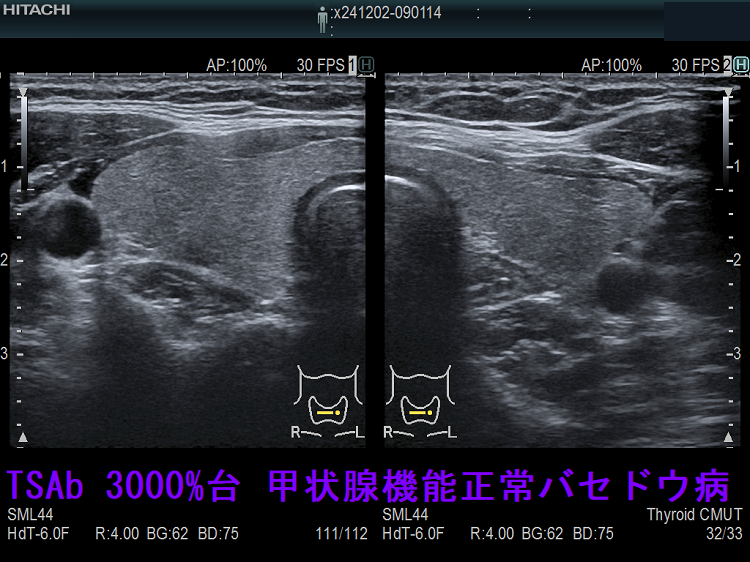

TSAb(TSHレセプター抗体[刺激型]; 甲状腺刺激抗体) 3000%台(正常値<110%)なのに甲状腺機能正常のケースがありました。おそらく、TSBAb(TSHレセプター抗体[阻害型]、甲状腺刺激阻害抗体)とTSAb(甲状腺刺激抗体) が拮抗していると考えられますが、TSBAb(甲状腺刺激阻害抗体)は保険適応外のため測定できませんでした。本当、何とかして欲しいものです。

TSAb(甲状腺刺激抗体) 3000%台 甲状腺機能正常バセドウ病